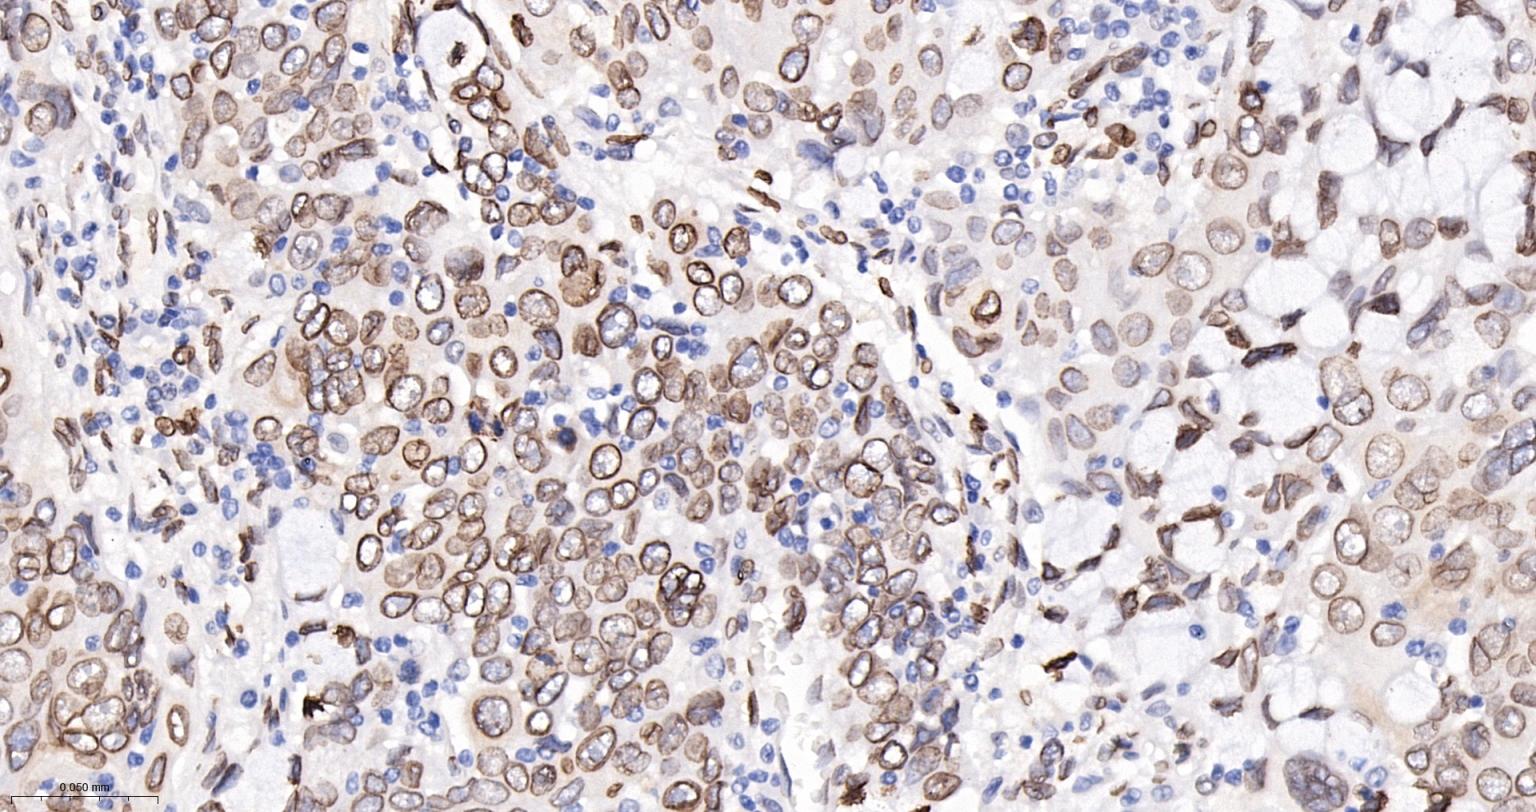

Paraformaldehyde-fixed, paraffin embedded Human Breast; Antigen retrieval by boiling in sodium citrate buffer (pH6.0) for 15 min; The section was incubated with Lamin A/C Monoclonal Antibody, Unconjugated (bsm-62886R) at 1:400 overnight at 4°C, followed by conjugation to the bs-0295G-HRP and DAB (C-0010) staining.